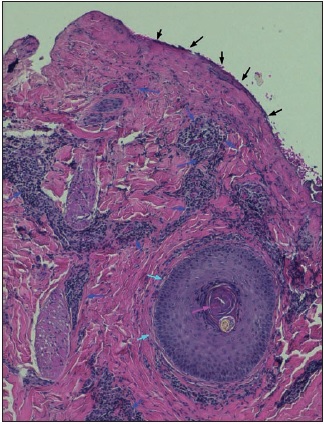

En 3 de los casos presentados, previamente a la aplicación de Nexobrid®, solicitamos el consentimiento del paciente o de su familia para la realización de una biopsia pre y postratamiento mediante punch de 5 mm para estudio histológico mediante tinción de hematoxilina-eosina. En el primer caso (Tabla I, caso 9) practicamos la biopsia por tratarse de una quemadura de aspecto profundo en la mano, a fin de valorar si el desbridamiento enzimático histológico era completo. En el segundo caso (Tabla I, caso 11) para valoración de la selectividad del desbridamiento de una quemadura en pierna con aspecto de afectación dérmica parcial y así comprobar si existía preservación de la dermis sana. En el tercer caso (Tabla I, caso 12) para valorar si el desbridamiento enzimático histológico había sido completo en quemaduras en miembros superiores de un paciente al que habían aplicado Flammazine Cerio® (Alliance Pharmaceuticals Ltd., Reino Unido) en otro centro, antes del tratamiento enzimático con Nexobrid®.

Estas biopsias nos permitieron realizar una valoración histopatológica de la profundidad de las quemaduras, correlacionar los hallazgos histológicos con la valoración clínica, y evaluar la selectividad y la eficacia del desbridamiento enzimático. Tomamos 2 muestras por paciente: la muestra pretratamiento se seleccionó en aquella zona de la quemadura que clínicamente pareció de mayor profundidad, y la muestra postratamiento de la zona adyacente a la muestra pretratamiento, y con aspecto clínico de similar profundidad.

La realización de biopsias pre y postratamiento en 3 de los pacientes permitió observar 2 casos de desbridamiento parcial de la zona necrótica, siendo 1 caso una quemadura de tercer grado en dorso de mano que precisó de injerto (Fig. 25 a 34, caso 9), y el otro una quemadura previamente tratada con Flammazine Cerio® (Fig. 35 a 45, caso 12). En el tercero de los pacientes biopsiados apreciamos desbridamiento histológico completo de la zona necrótica con preservación de la dermis sana (Fig. 46 a 50, caso 11). Como hallazgos significativos, en las 3 muestras postratamiento evidenciamos un infiltrado inflamatorio linfocítico perivascular (Fig. 36, 40 y 48).

Uno de los aspectos más interesantes y novedosos de nuestro estudio son los hallazgos de los estudios histopatológicos. Una de las ventajas que parece tener Nexobrid® es la facilidad para el diagnóstico visual de la profundidad de la quemadura, que enlaza con la posibilidad de cubrir con injertos aquellas quemaduras que ya vemos que son de tercer grado, permitiendo un tratamiento conservador en aquellas zonas donde existe dermis viable. Nuestras 3 biopsias muestran una correlación del 100% con el diagnóstico clínico de profundidad de la quemadura tras el desbridamiento enzimático. Este diagnóstico no lo pudimos realizar antes de la aplicación del producto, ya que eran zonas de profundidad indeterminada, difíciles de valorar clínicamente antes del desbridamiento enzimático. Presentamos esta conclusión como uno de los puntos fuertes del tratamiento enzimático, ya que además de las implicaciones de la eliminación precoz de la escara, la facilidad de diagnóstico visual de la profundidad de la quemadura podría implicar un abordaje más fácil de las lesiones a la hora de decidir si injertar o si esperar a la epitelización espontánea.